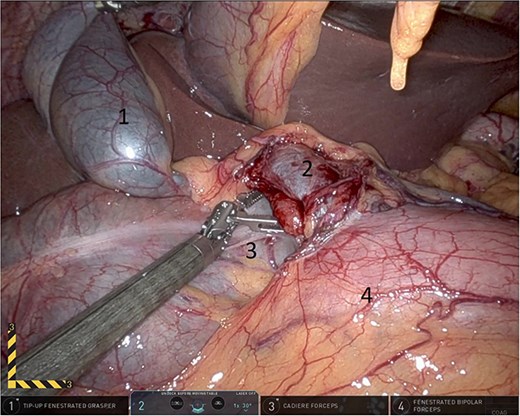

Upon entering the abdominal cavity, dilated bowel loops were observed (Fig. 2), and a significant portion of the colon was found herniated through the foramen of Winslow (Fig. 3). The herniated colon was covered by the pars flaccida (Fig. 4) (Video S1). Careful dissection was performed anterior to the hepatoduodenal ligament (Fig. 5). The gall bladder was retracted to the patient's right upper quadrant, which allowed for the retraction of the foramen of Winslow (Fig. 6) (Video S1). After carefully placing the tip of the instrument posterior to the portal vein and gently elevating it, the herniated colon was successfully reduced (Fig. 7) (Video S1).

Herniated colon through the foramen of Winslow (1: incarcerated colon, 2: hepato-duodenal ligament, 3: herniating colon, 4: the liver).